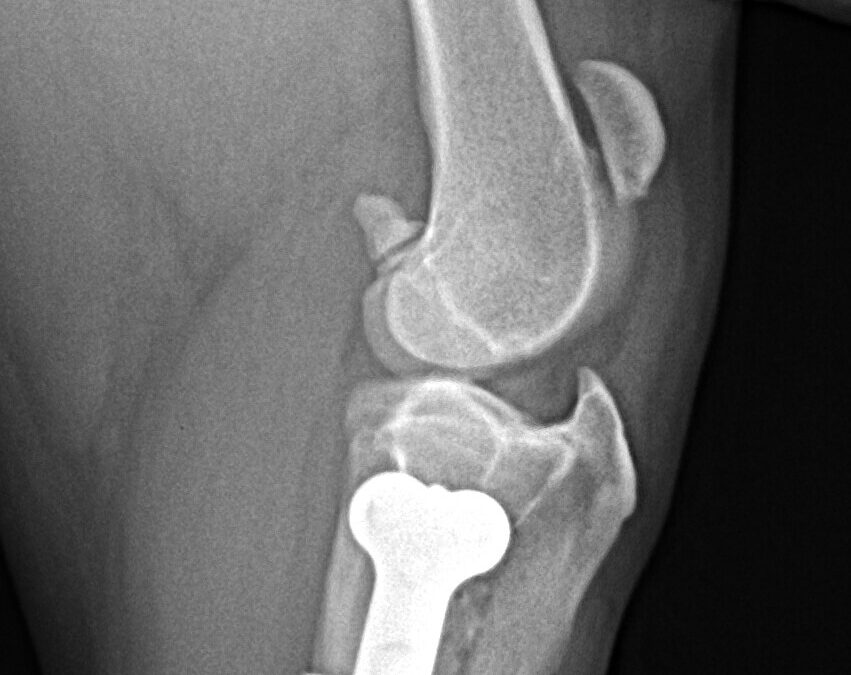

Miles-Houghton-TTO-1-year-later-recovered_2